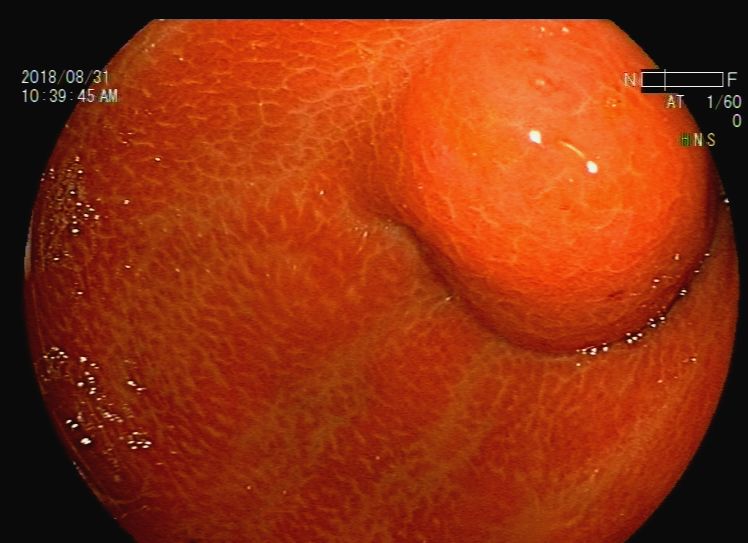

胃镜检查:反流性食管炎,胃内液体潴留,吻合口前区黏膜下隆起——考虑转移灶压迫,近端小肠梗阻(图9、图10、图11、图12、图13)。根据消化道造影及内镜检查结果,考虑梗阻部位在近端小肠,吻合口前区虽有较大的隆起灶,但是内镜通过可,暂不处理。

图11 胃镜检查见胃流出道前区隆起灶,考虑胃壁外压病灶